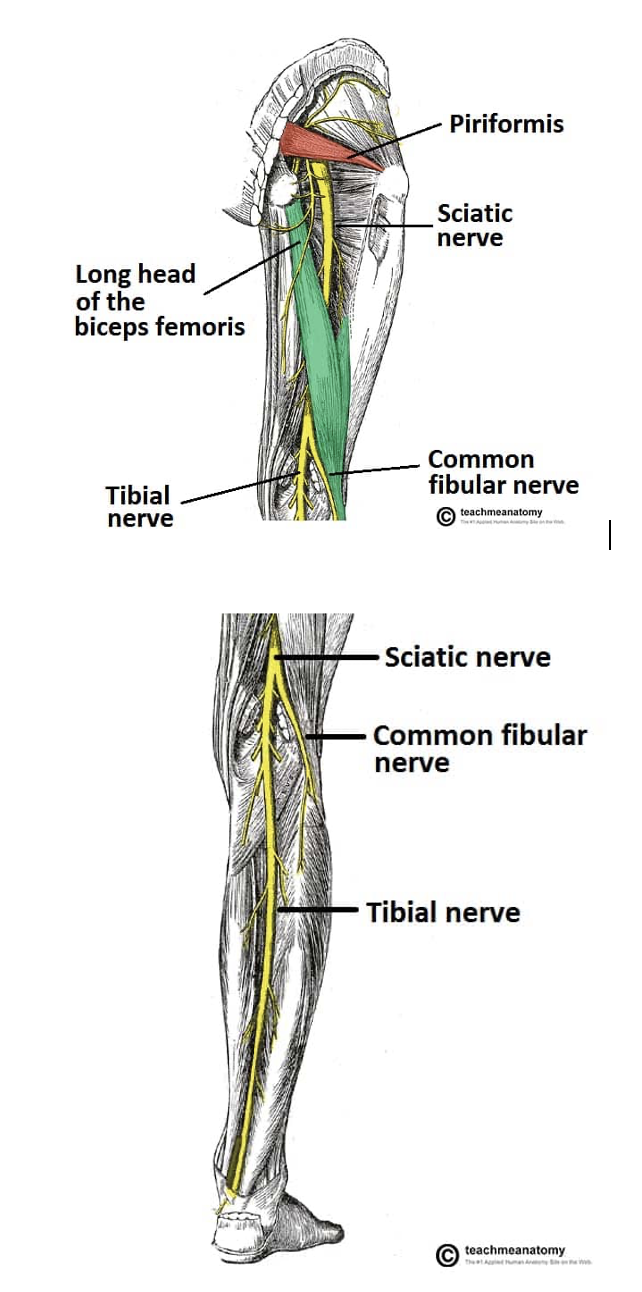

Sciatic Nerve + Branches

Sciatic nerve (sensory and motor)

Tibial nerve (sensory and motor)

Common fibular/peroneal nerve (motor) L4-S3